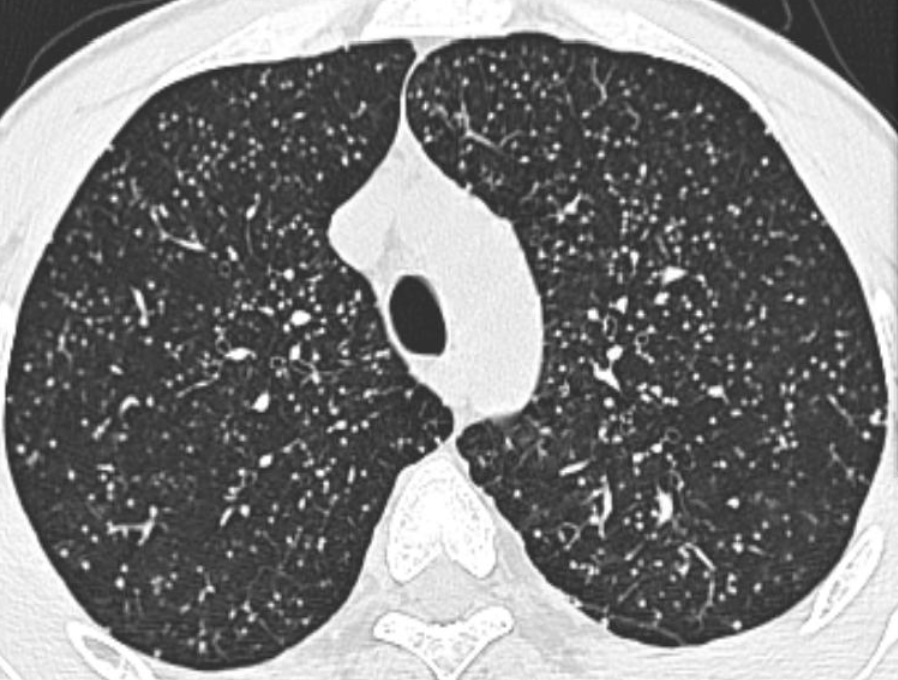

2. 血行播散性肺结核:急性血行播散性肺结核表现为两肺均匀分布的大小、密度一致的粟粒阴影;亚急性或慢性血行播散性肺结核的弥漫病灶,多分布于两肺的上中部,大小不一,密度不等,可有融合。需与电焊工尘肺、肺转移瘤等其他疾病鉴别。

*血行播散性肺结核:均匀分布的大小、密度一致的粟粒结节

*误诊为血播肺结核的电焊工尘肺,弥漫性肺病都必须询问职业史,无发热的血行播散性肺结核诊断需谨慎

*甲状腺癌肺转移:27 岁女性,双肺弥漫性粟粒影,误诊为血播,因无发热,质疑诊断,最后确诊为甲状腺癌肺转移。